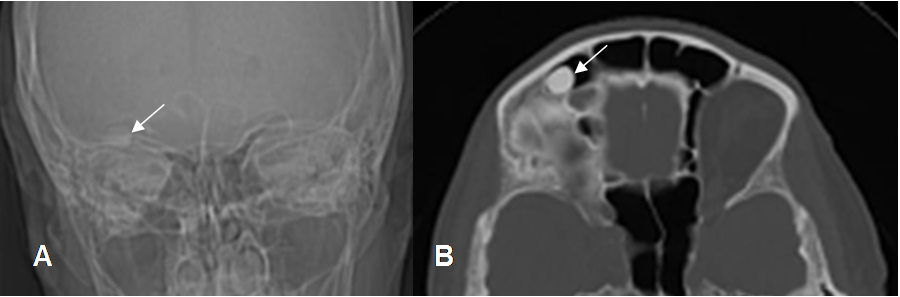

Fig 54. Osteoma.

Mayor frecuencia entre la 4º y 5º décadas. Predominio en cráneo, cara y huesos largos.

Lesión metafisodiafisiaria, de ubicación cortical.

Fig 55. Osteoma,

A: Rx AP y B: TAC axial. Imagen densa y homogénea, en relación con el seno frontal derecho por osteoma.